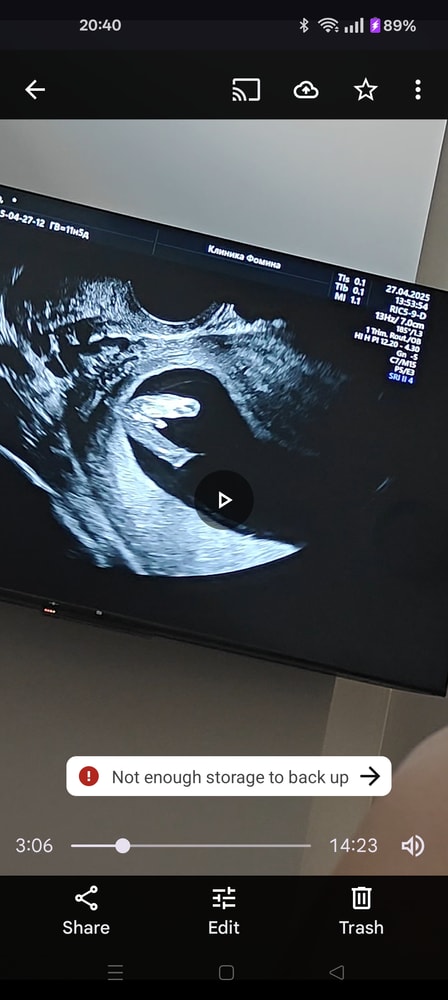

11+5, 1й скрининг (определение пола)🤭

Вчера были с мужем на 1м скрининге нашей козявочки. Все хорошо, все соответствует нормам 🙏

Парень у нас с характером, на камеру работать не хотел, а хотел приватности. Датчик УЗИ его конкретно так бесил, поэтому на всех снимках он в процессе разворота от нас 😁 Не тут-то было.

P.S. Пол мы узнали ещё в 10 недель благодаря НИПТ, но муж захотел "сам посмотреть"🤭 Ну, кхм, теперь у нас есть фото наследника 18+ 🫣 Выложу его в комментариях для девушек, гадающих по половому бугорку. Вам для инфо: на экспертном УЗИ аппаратура позволяет "повертеть" малыша во всех плоскостях, так что пол можно разглядеть достоверно. Направление съемки указано на 1м фото, а на 2м его результат.